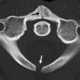

Compensatory hypertrophy with contralateral neural arch deficiency

Enlarged vertebral pedicle